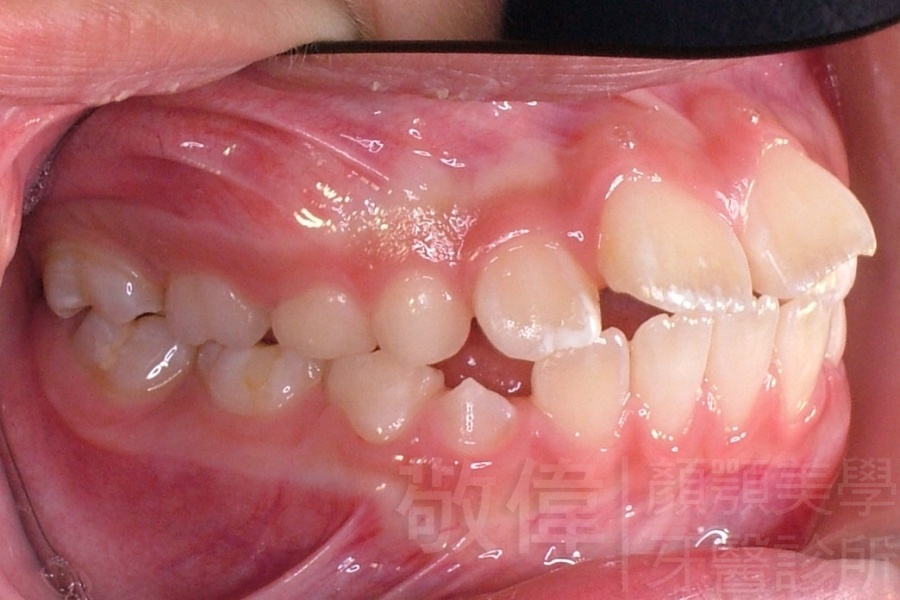

齒顏矯正/扭曲的牙弓和暴出的虎牙的矯正

矯正前-右   矯正前-正   矯正前-左

矯正後-右   矯正後-正   矯正後-左

<個案說明>

原來混亂歪七扭八的牙齒,尤其是暴牙(俗稱虎牙),笑起來不好看且沒有自信的笑。經由矯正之後,牙齒變的更健康,更能展現出自信的笑容。